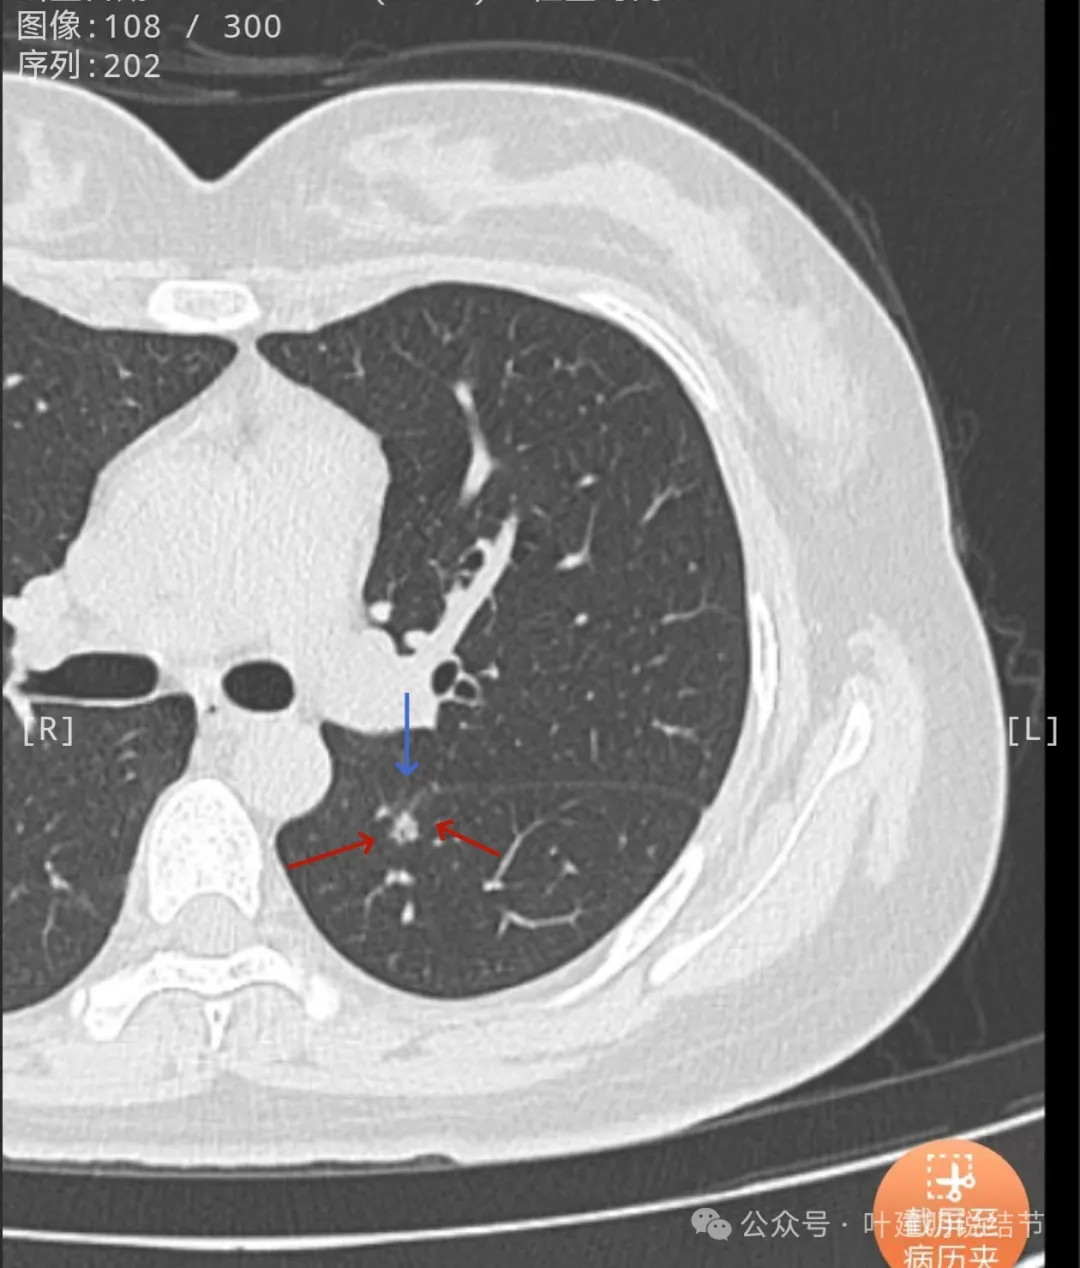

轮廓清,小空泡征明显,密度较高,基本上是实性。

边缘区密度较淡。